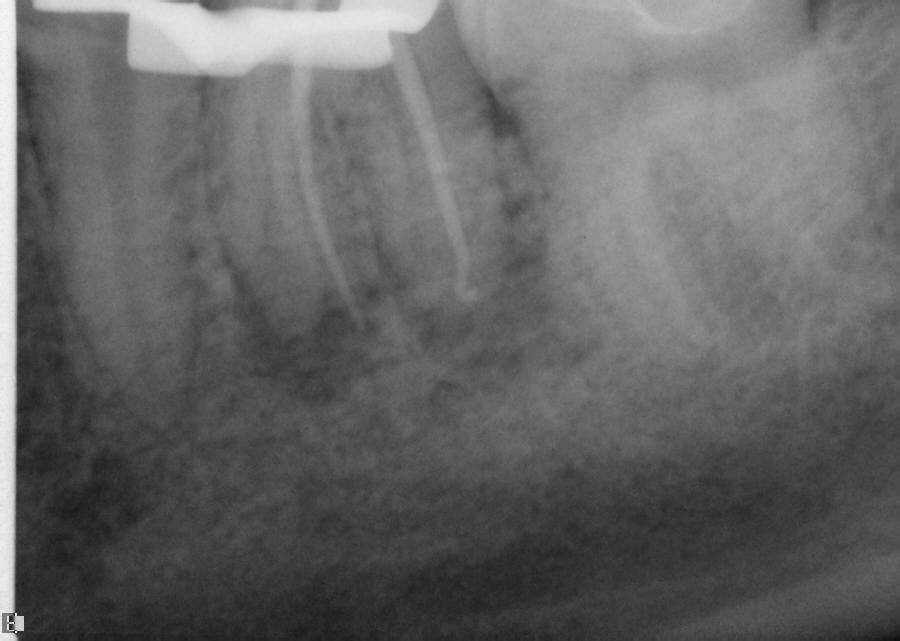

The question remains: how often should clinicians use apex locators, and are they really necessary? Because studies have shown them to be up to 96% accurate,8 it stands to reason that they could be used in every case possible. In some instances, the apex cannot even be seen radiographically. In these cases, using an apex locator is imperative to finding the true working length of the canals. The question remains: how often should clinicians use apex locators, and are they really necessary? Because studies have shown them to be up to 96% accurate,8 it stands to reason that they could be used in every case possible. In some instances, the apex cannot even be seen radiographically. In these cases, using an apex locator is imperative to finding the true working length of the canals. Figure 10 and Figure 11 through Figure 14 demonstrate two such cases; they likely would not have been successfully completed without the use of an apex locator. Even the final PA (Figure 14) does not clearly depict where the canals end.

Working films or radiographs, however, should not be completely eliminated from the clinician’s armamentarium. While practitioners may legally only be required to depict a preoperative and postoperative radiograph, from an endodontic point of view at least one working radiograph should always be taken. This does not mean that a master file radiograph has to be taken; however, it is prudent to take one in cases in which the anatomy is challenging, and the author recommends always taking a master cone radiograph (Figure 11 through Figure 14).

The master cone PA is the last indicator clinicians have in assessing whether or not their working lengths were truly accurate. This radiograph is crucial in affording the practitioner the opportunity to make adjustments to properly complete the procedure to the desirable lengths. An example is presented in Figure 15 through Figure 18. Figure 16 and Figure 17 show a master cone PA that demonstrates two of four canals to proper length. After adjusting the length of the other two master cones, the clinician was able to correct the lengths to produce a more appropriate result, as seen in Figure 18.